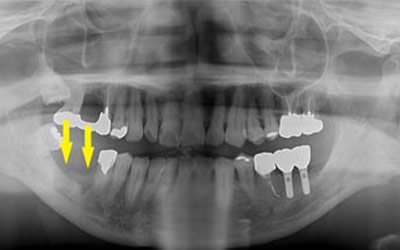

患者様のインプラント治療前のレントゲン写真です。右下顎大臼歯2本の抜歯後のレントゲン写真で、写真の黄色矢印は、歯の周囲の歯槽骨が大きく吸収されてしまっていました。

写真のように、CTで見ると、骨吸収の様子が良く分かり、下顎骨の中を通る神経近くまで骨がありませんでした。

さらに、CTで、別な方向から見ると、黄色矢印のように骨が吸収されていて、緑色矢印で示される神経の通る管に迫り、インプラントが埋入できるような骨量はありませんでした。

インプラントを埋入するために、骨を増やす方法はいくつかありましたが、この場合、患者様ご自身の骨をブロック状で移植するのが最も適していると判断し、自家骨移植術を行ないました。患者様ご自身の下顎前歯の下方から骨を採取して、骨がなかった部位に移植し、スクリューで固定したCT画像です。黄色矢印部分が、2つの骨片を移植して、固定したところです。

手術後の、別な方向からみたCT画像です。術前に大きく吸収されていた部分に、骨のブロックが移植され、骨が造成されています。真っ白にピンのように写るのは、骨を固定した小さなスクリューです。

移植した骨が周囲の骨と、結合したのを待ち、6か月後に、インプラント埋入手術を行いました。下の写真が、インプラント埋入後のCT画像で、黄色矢印に示すように、インプラントが2本埋入できました。

インプラント埋入後の、別な方向からみたCT画像です。神経の通る管にややギリギリでしたが、神経は傷つけずに、インプラントが埋入できました。この後、4か月ほどで、咬む歯の部分、上部構造を完成させました。